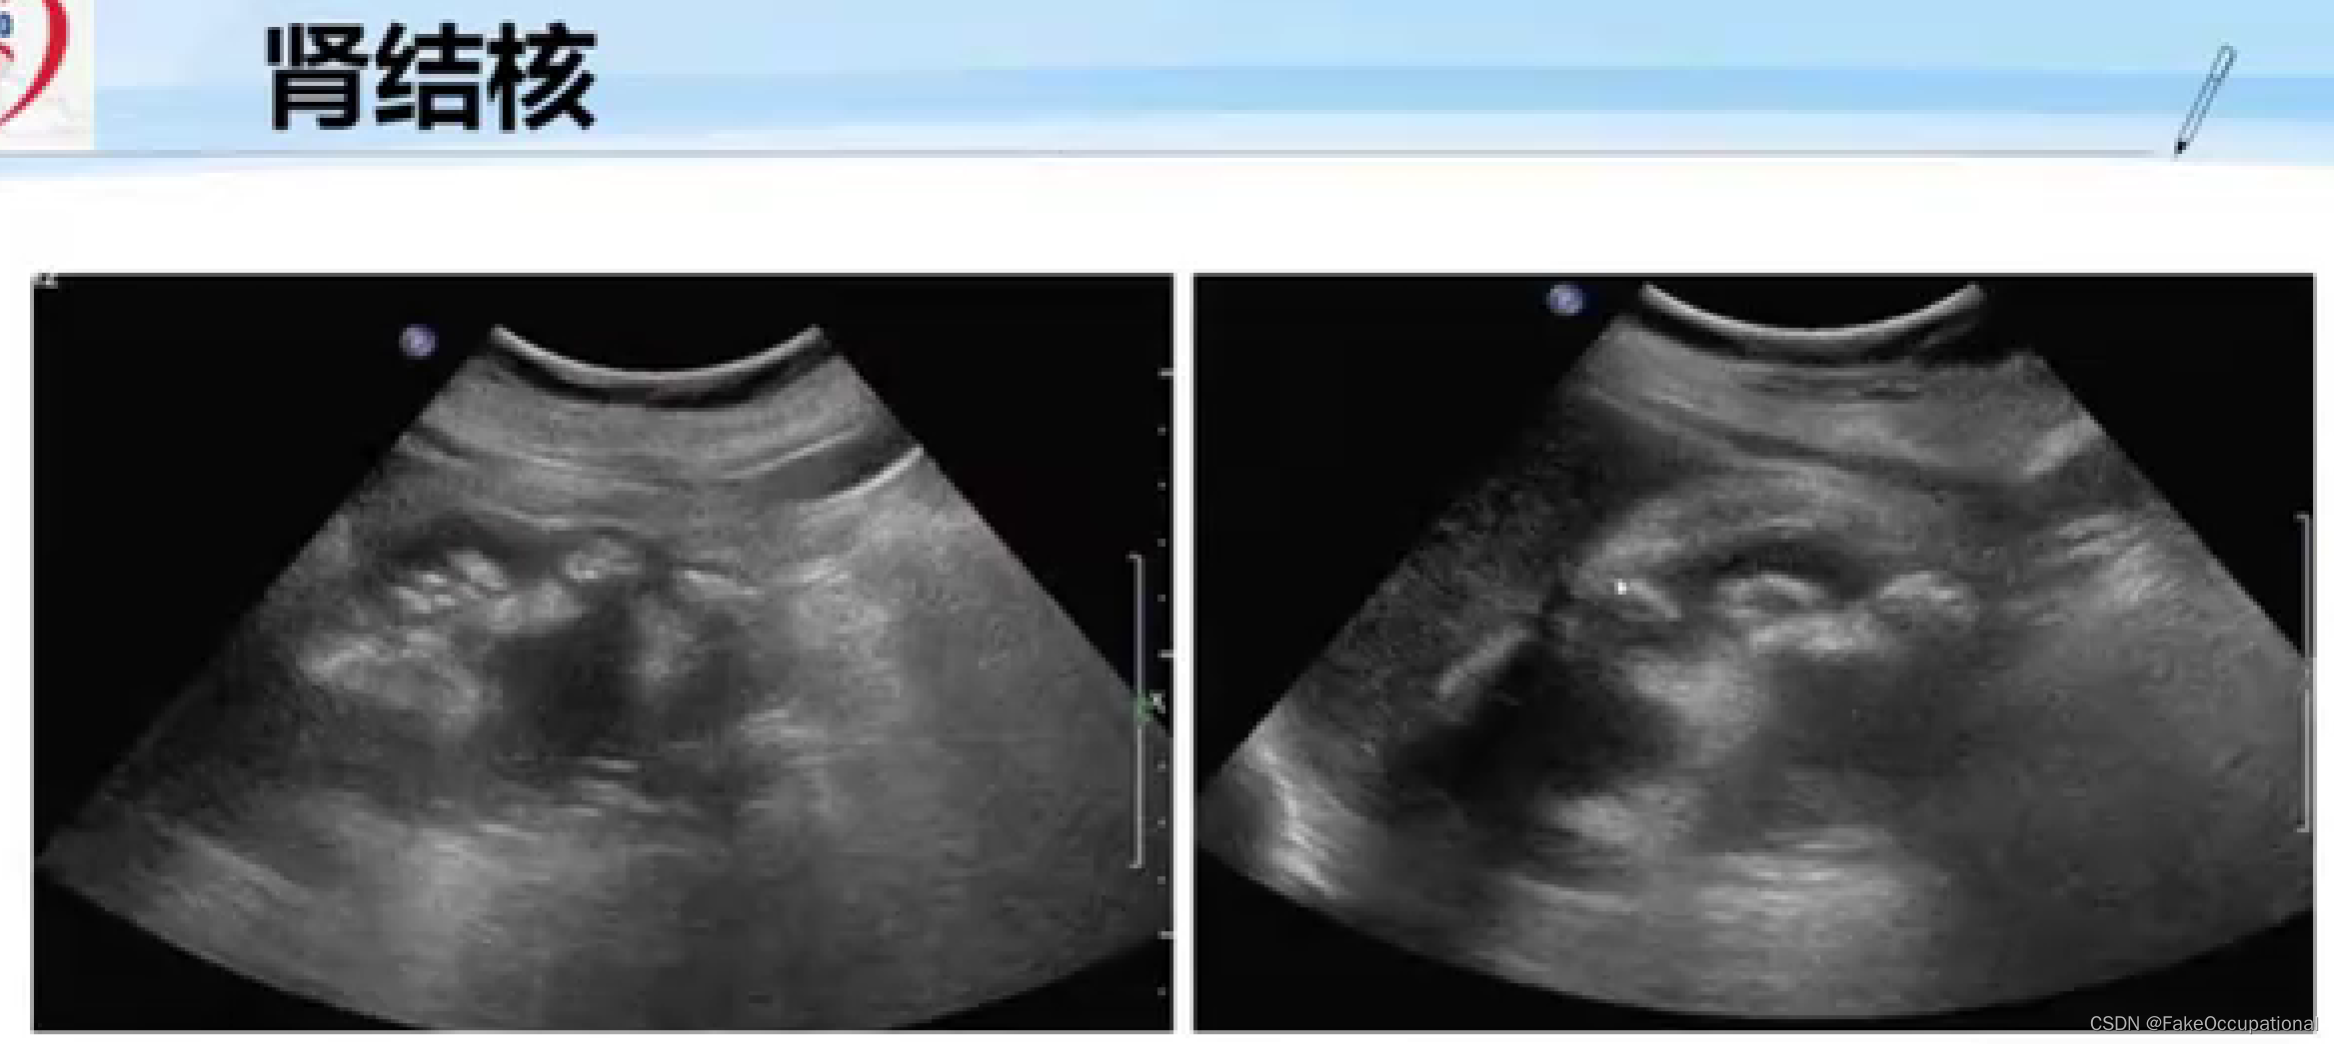

正常肾脏及肾血管超声表现

-

与正常肾脏造影相比,慢进快退

-

肾结核的超声显示的内部结构几乎完全消失

-

第三张图为CT结果